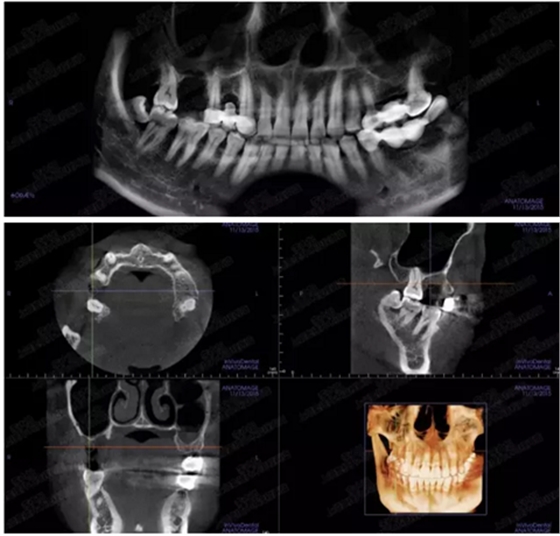

病例四

剩余骨量2mm-5mm且存在斜形竇底

007.png

提升8mm

008.png

009.png